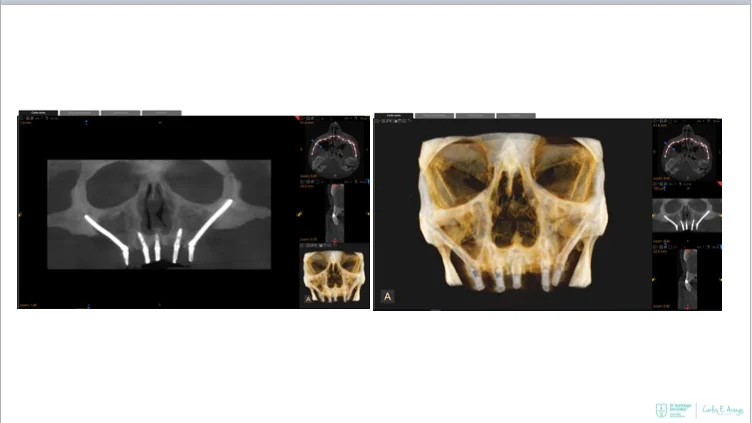

Two straight anterior implants and two implants tilted up to 45º in the posterior - Immediate Function (fixed provisional bridge)

For patients meeting criteria for immediate loading of implants - Graftless Procedure: Bone grafting is avoided by tilting the posterior implants, utilizing available bone.